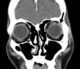

Lacrimal gland inflammation

The lacrimal glands are paired exocrine glands, one for each eye, found in most terrestrial vertebrates and some marine mammals, that secrete the aqueous layer of the tear film. In humans, they are situated in the upper lateral region of each orbit, in the lacrimal fossa of the orbit formed by the frontal bone. [Source: Wikipedia ]